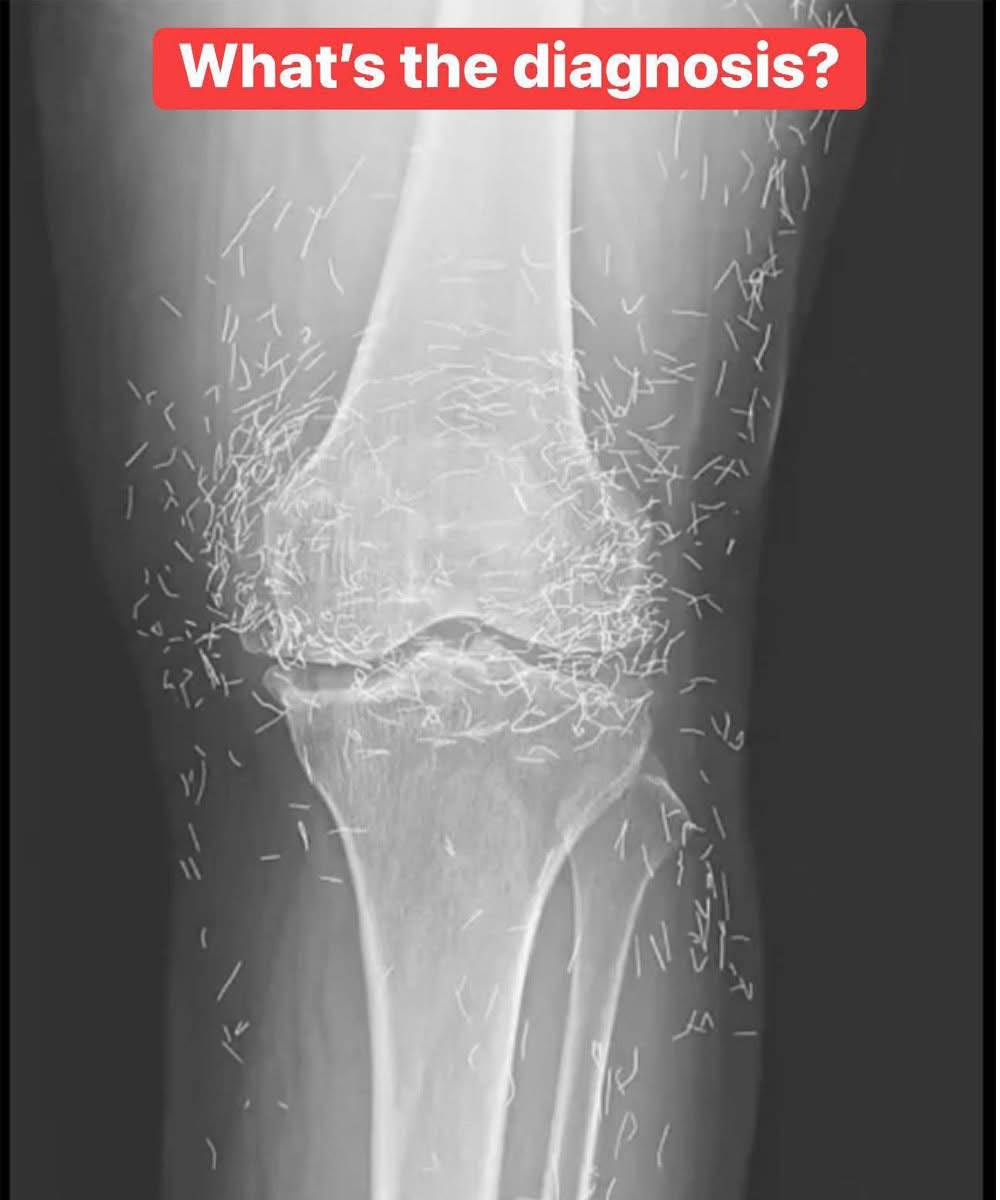

X-Ray Reveals Hundreds of Gold Needles in Woman’s Knees

A 65-year-old woman in South Korea discovered the surprising cause of her chronic knee pain: hundreds of tiny gold acupuncture needles embedded in her joints.

Her therapy involved a controversial method in which gold needles are inserted and left in the body, supposedly to provide ongoing stimulation. Some practitioners believe this can reduce pain for arthritis patients.

But according to the New England Journal of Medicine, the practice can be dangerous. Experts warn that leaving foreign objects inside the body often triggers inflammation, infection, or abscesses as the immune system tries to fight them off.

Dr. Ali Guermazi, a radiology professor at Boston University, explained that embedded needles can also complicate imaging tests. “The human body wants to expel foreign objects,” he said, noting that scar tissue can form around them, obscuring X-ray details.